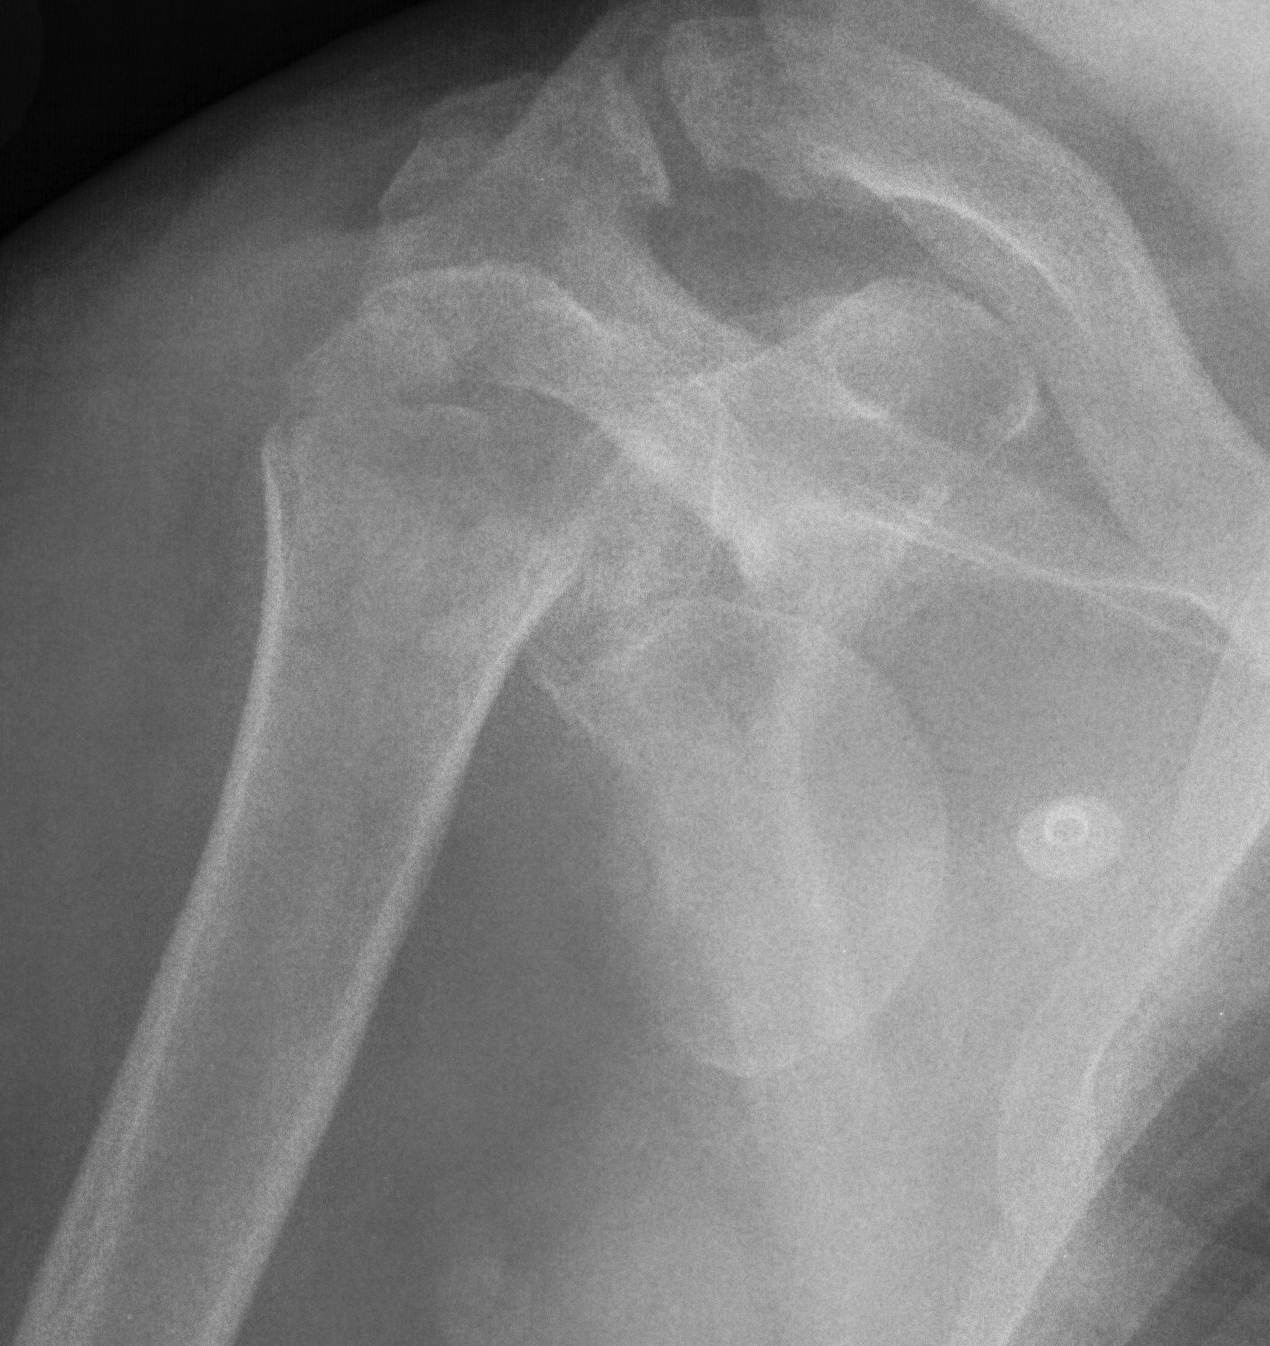

proximal humerus fracture Background ORIF with locking plate Arthroplasty Greater tuberosity fractures Lesser tuberosity fractures / avulsions Book traversal links for Proximal humerus fractures ‹ Pectoralis Major Tears Up Background ›